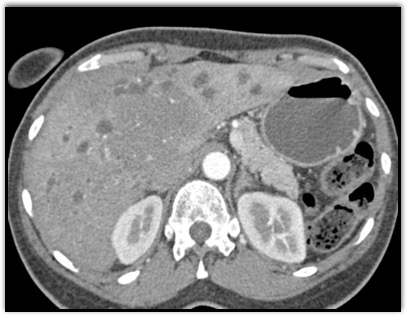

The least likely diagnosis in this case is?

cholangiocarcinoma

lymphoma

carcinoid tumor

hepatoma